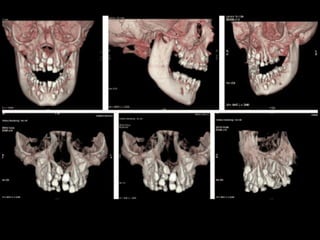

Panoramic (reconstructed from CT)

The most likely diagnosis for the facial asymmetry of this young girl is an

undiagnosed condylar fracture that most likely happen when she falled on a meta

crossbar bar ladder 2 or 3 years ago while she was 4 - 5 years old or so. The

condylar stump has healed and a new condylar head has formed, but the losted

substance of the condyle is gone. Therfore, the height of the ramus has

shortened.

The left ramus and condylar neck are shorter and the left eminence has no slope

if any. Healing and normal growth had reshaped both condyle and eminence.

!

Read more

When looking to the condyle from an anterior view, one can see the oblong

shape of a condyle but the left condyle is smaller.

The midline are not coincident. Note that the lower midline is toward right like

the occlusal plane canting to the right. This can be explained by the lack of

heigh of the left ramus and as normal growth occur, there is a wagon wheel

effect and the midline deviate toward the normal side, the occlusal plane is

moving up on the affected side.